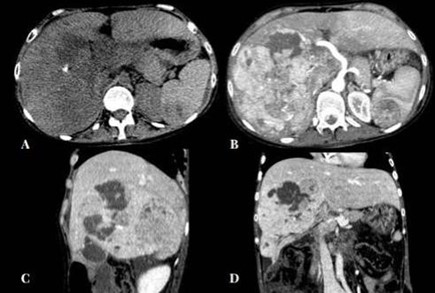

Hepatocarcinoma fibrolamelar

El carcinoma fibromelar hepatocelular es poco frecuente y representa menos de 1% de todos los casos. Se presenta principalmente en adolescentes y adultos jóvenes como una masa tumoral hepática única, con frecuencia de gran tamaño, sin asociación con cirrosis y rodeada de una cápsula fibrosa. En la tomografía multicorte, sin contraste, se observan tumores hipodensos heterogéneos con una cicatriz central muy hipodensa. También puede haber áreas de necrosis y calcificaciones. Son lesiones hipervasculares con captación intensa pero heterogénea (Anexo 15) del medio de contraste en fase arterial, la captación en fase portal y de equilibrio son variables y la cicatriz central, los septos y la cápsula del tumor son hiperdensos en fase tardía, incluyendo en los estudios de RM.(18-19)